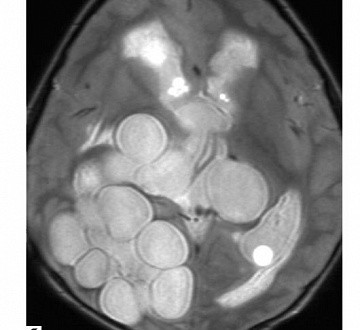

КТ-снимок токсоплазмоза головного мозга

P.S. Ну и как, например, __вот это__ «вылечить»? От тела можно отрезать лишнее, оно или растянется, или нарастет (если не полтуловища, канеш). С моском это не сработает...

@𝕵𝖔𝖍𝖆𝖓 ⛧ не в состоянии что-то разглядеть на такого рода снимках, для меня это выглядит как неведомая грамота.

@erua Ну, это крайний случай, небось, на фоне вичухи, но в двух словах — мозгам пиздец.